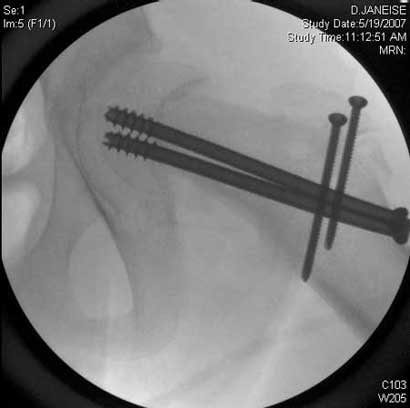

Severe slip treated with arthroscopic Dunn type of femoral neck osteotomy

Severe slip treated with arthroscopic Dunn type of femoral neck osteotomy, reduction and fixation.